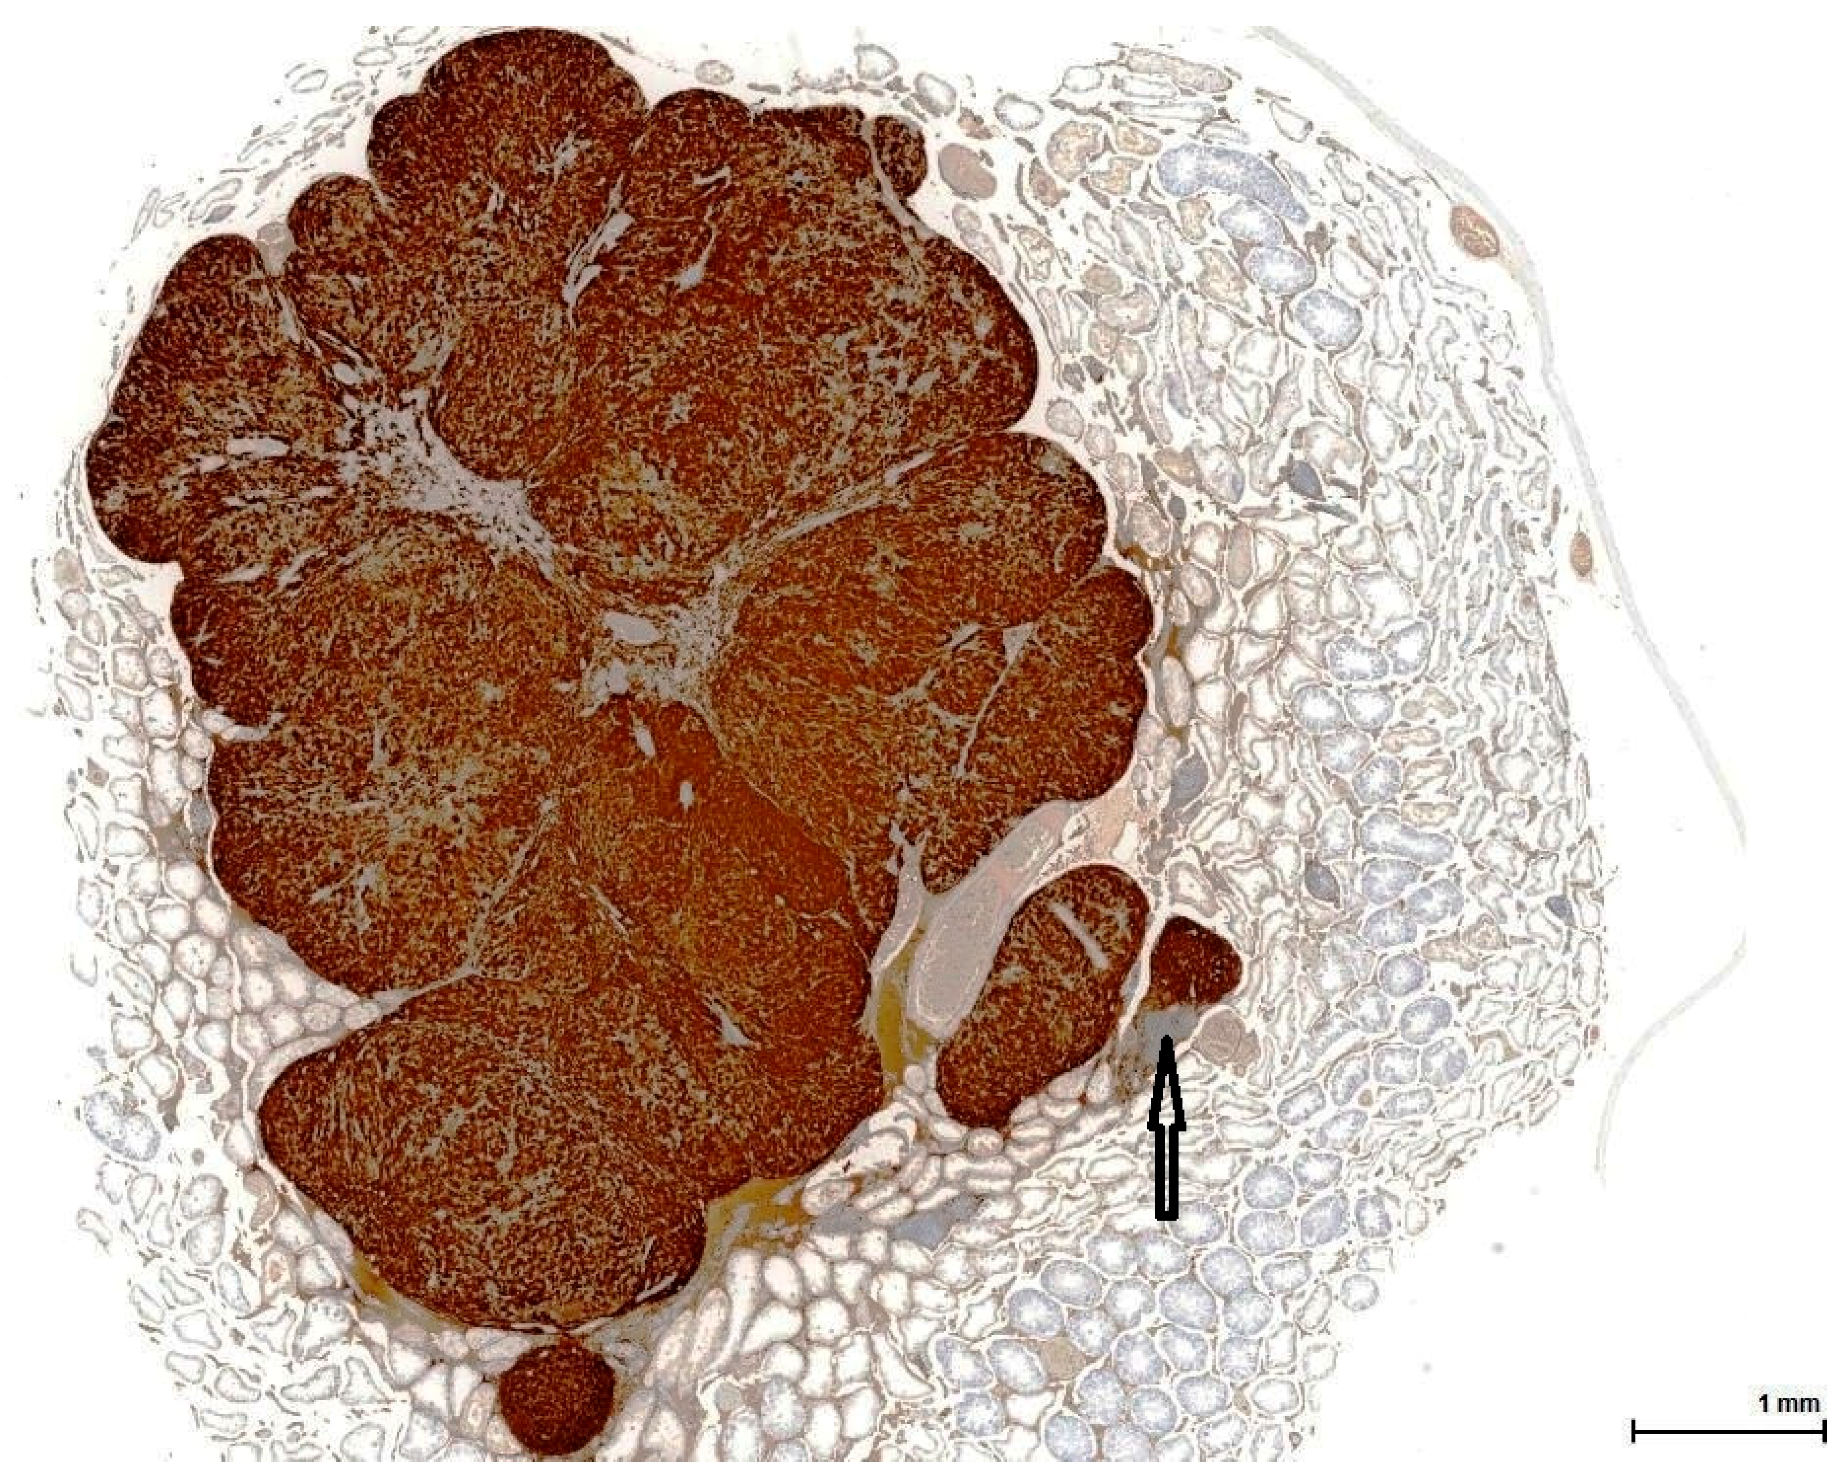

Figure 5. Control rat testis from NTP study on OTA (Case 6, Table 2). Intense and diffuse positive immune reaction (brown) with small cell negative area (arrow) (Calretinin).

Figure 6. Control rat testis from NTP study on OTA (Case 6, Table 2). Tissue section adjacent to that in Figure 5. Variably positive immune reaction for Melan A (brown) with small cell negative area (arrow) (Melan A).

The OTA-treated cases as well as the controls are positive for Calretinin (Figure 5) and Inhibin A to various degrees and in different distributions. This immune profile is supportive of sex cord-stromal origin; the positive immune reaction for Melan A (Figure 6) is suggestive of a Leydig cell tumour.

Calretinin is a calcium-binding protein expressed by a large range of cells or tissues. In the testis, Sertoli cells and Leydig cells are positive, as well as the rete testis epithelium; in clinical practice it is used mostly to establish the mesothelial origin of a pleural tumour (mesothelioma). In our study, the majority of large neoplastic cells (OTA-treated and controls alike) show a diffuse and intense immune staining of the cytoplasm (fine, vesicular): the small basophilic cell component is rather negative, while the intermediate cells are only weakly and inconstantly positive (Figure 7).

Melan A is a melanocyte-specific cytoplasmic protein involved in the melanosome formation of the skin. In the ovary and testis, it is positive in steroid-producing cells due to antibody cross-reactivity to an unknown molecule in these cells; these cells do not produce Melan A. The large neoplastic cells of OTA-treated rat tumours show areas of strong granular cytoplasmic staining reaction (Figure 9), but negative areas as well, especially composed of small cells. In controls, the immune reaction is weaker to negative in two cases, present sometimes with granular pattern in the large cells component, and focally stronger in small cell areas.